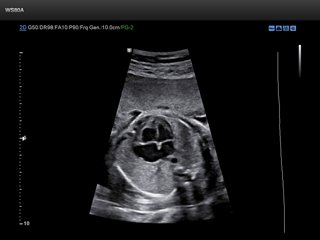

Atlas of ultrasound images - obsterics (pg. 5)

In the section "Оbsterics" of atlas the results of ultrasonic examinations of pregnant women with different durations of gestation are represented. Here you can see images of internally organs, cerebrum, cordis and the sex of the fetus, the sonograms of multiple pregnancy, the blood flow in placenta and umbilical cord, defects of fetal`s development, etc.